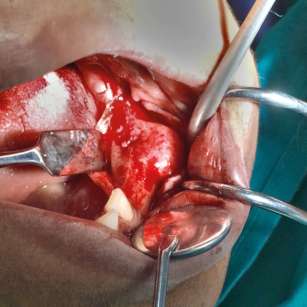

| Terapia chirurgica | Correzione di deformità, stabilizzazione di fratture, decompressione nervosa, miglioramento estetico. | Approcci conservativi (curettage, rimodellamento) presentano un rischio di recidiva. L’escissione radicale con ricostruzione offre maggiori tassi di successo. La strategia dipende dalla localizzazione, come nella classificazione di Chen e Noordhoff per il distretto cranio-facciale: Zona 1 (fronto-orbitale) consente resezioni radicali; Zona 2 (regioni craniche coperte) consente resezioni radicali, ma in grado minore rispetto alla zona 1 Zona 3 (base cranica centrale) richiede approcci conservativi per il rischio a nervi e vasi; Zona 4 (area dentata) predilige metodi conservativi per preservare la funzione dentale. |